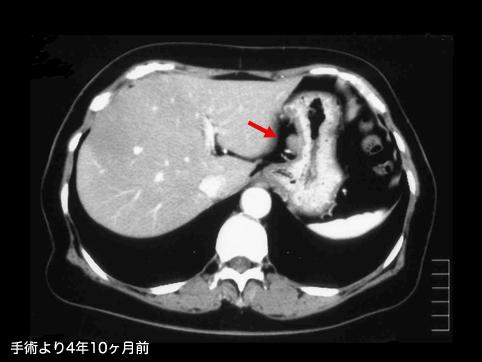

A case of gastrointestinal stromal tumor that extraluminally developed in size during four years and ten months.

[Image-ID:11341]

질환(병리주체)의 분류

악성 비상피성종양/평활근육종

부위(장기별)

위(부위)/체부

검사방법

CT

종양의 최대경(밀리미터)